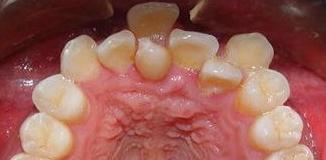

三、爱吃手看起来有点萌其实危害大生活中的一些不良习惯也是会导致牙齿不齐的。

比如宝宝换牙时,总喜欢用舌头去舔牙,可能就把牙齿舔歪了,不过这个不太好发现,毕竟是宝宝嘴里的活动,可以提前告诉小朋友如果发现了及时制止。

还有的宝宝会有咬东西的习惯,家长一看「哎呀宝宝自己玩儿的挺好挺安静,吃会儿就吃会儿吧!给ta洗干净手让ta吃个够」这一吃个痛快,时间长了就可能会导致牙齿长歪。

发现没有,很多所谓的「门牙稍息的多多少少都和咱们小时候挂钩,如果当时能够及时发现尽早干预。基本上都是一些很快很好解决的小问题,当然也可能是遗传啊智齿啊牙弓狭窄等造成门牙歪斜。成年后,当初的小问题就变成需要花更多钱更多时间的大问题了,甚至可能需要拔牙解决。不如早点儿行动,现在多和你的牙医朋友南先森聊天,未来就少一个因为「稍息牙」不敢张嘴笑的大朋友~